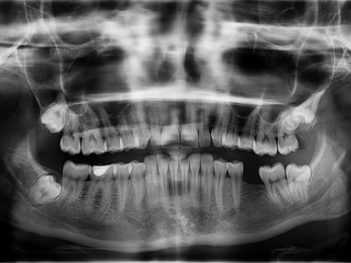

Did you know that tooth loss can lead to poor nutrition and is linked to many systemic diseases, like diabetes and coronary heart disease. A person’t psychological well-being and ability to function in the everyday world can also be affected. According to the Centers for Disease Control and Prevention, nearly 40 million Americans have no teeth in one or both jaws.

- In previous decades, removable dentures and conventional bridges were the sole means of replacing teeth. Now dental implants offer improved function and comfort and are mechanically and biologically superior to previous options.

“When you lose even a single tooth, it will result in bone loss, change the bite and result in adjacent teeth moving toward the missing space. The longer a person waits to get it replaced, the more challenging the clinical situation,” Grant added.